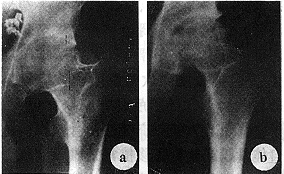

摘 要 1990年5月~1994年4月,对42例(47个髋)关节软骨全厚缺损患者采用冷冻保存胚胎颅骨骨膜移植进行修复,其中14例股骨头骨质Ⅳ期坏死者,同时施行带旋髂深血管蒂髂骨植骨。对34例(38个髋)进行了2年~6年(平均40个月)随访。结果表明,按照吴之康髋关节人工置换术后疗效评定标准,优良25例,很好5例,好3例,尚可1例。认为,与自体移植物修复关节软骨大面积缺损相比,这种方法无附加损伤,具有移植材料、形态与股骨头相似等特点,是治疗髋关节软骨大面积缺损的一种有效方法。

Abstract It is very difficult to repair large articular cartilage defect of the hip. From May 1990 to April 1994, 47 hips in 42 patients of large articuler cartilage defects were repaired by allograft of skull periosteum. Among them, 14 cases, whose femoral heads were grade. Ⅳ necrosis, were given deep iliac circumflex artery pedicled iliac bone graft simultaneously. The skull periosteum had been treated by low tempreturel (-40℃) before and kept in Nitrogen (-196℃) till use. During the operation, the skull periosteum was sutured tightly to the femoral head and sticked to the accetabulum by medical ZT glue. Thirty eight hips in 34 patients were followed up for 2~6 years with an average of 3.4 years. According to the hip postoperative criteria of Wu Zhi-kang, 25 cases were excellent, 5 cases very good, 3 cases good and 1 case fair. The mean score increased from 6.4 before operation to 15.8 after operation. The results showed, in compare with autograft of periosteum for biological resurface of large articular defect, this method is free of donor-site morbidity. Skull periosteum allograft was effective for the treatment of large articular cartilage defects in hip.